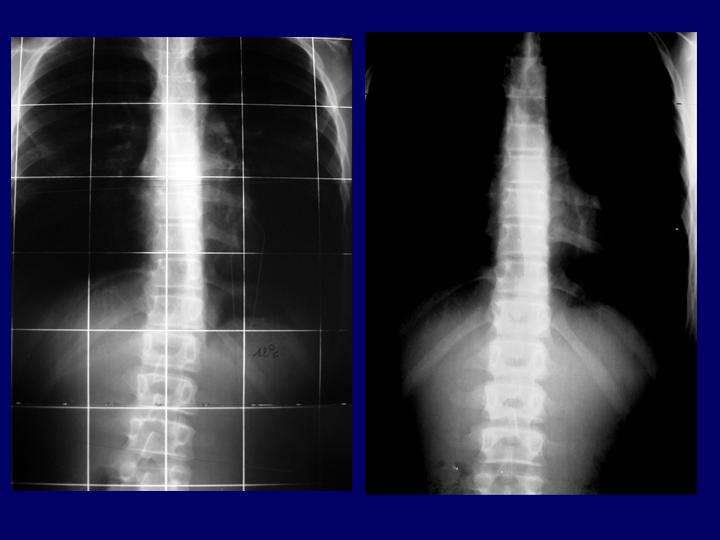

Hernias Discales